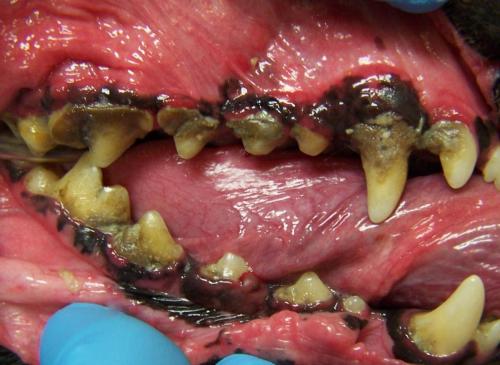

Grade III periodontal disease